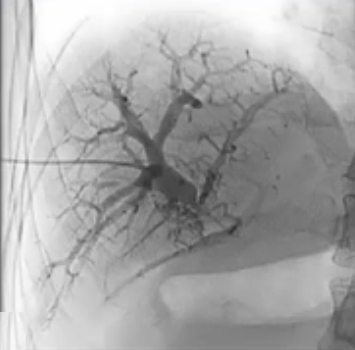

采用 TIPS 通路作为门静脉入路怎么样呢?

最初,在 PVT 病例中,经颈静脉入路是被考虑的主要通路。然而,这种方法试图进入血栓化或缺失的门静脉存在很高的难度。其可能造成的创伤,有可能使用溶栓药物/肝素的情况造成出血并发症。后来已经尝试了多种方法来改善这一通路。

TIPS 在慢性门静脉血栓形成伴海绵状变性中是被初始考虑的主要通路

在进行门静脉血栓治疗时施行经皮穿刺取栓术所增加的额外风险主要是由于创伤所致。 从技术层面来看,要穿刺进入血栓形成的血管是相当困难的,而且有可能会反复出现成功与失败的情况。 降低风险的方法包括对静脉瓣进行成像,或者安装一个装置来引导穿刺操作。

通过经皮经脾路径具有显著优势,能够使用 4Fr 细导管和导丝进行逆向再通操作,以 10 毫米的圈套器作为经颈静脉穿刺目标,通过Avitene 完成经颈静脉门静脉穿刺。